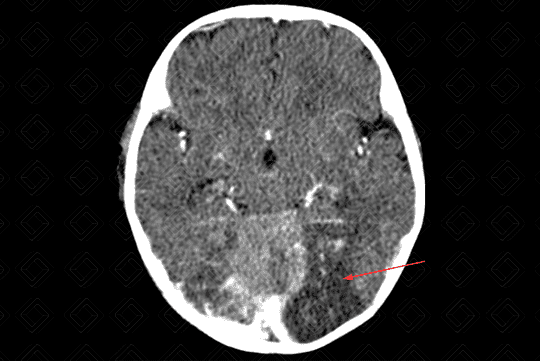

Texto alternativo para a imagem Figura 1. Créditos: Dra. Elazir Mota - Rio de Janeiro/RJ

Descrição da lesão: Acidente vascular encefálico isquêmico (AVE).

Descrição das figuras 1, 2 e 3: Tomografia computadorizada do crânio após a administração do contraste evidenciando extensa hipodensidade nas regiões parietal e occipital esquerdas com extensão ao tálamo deste lado (visualizado na reconstrução sagital), sem causar efeito compressivo, compatível com evento isquêmico subagudo (setas vermelhas).

Por volta de 24 a 72 horas, de fato, surge a hipodensidade do território vascular acometido (figuras 1, 2 e 3).